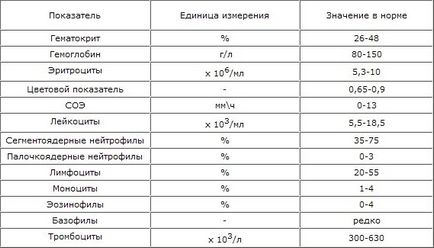

Прочети повечеВиж темата - индексите на кръвни изследвания при котки

Котки и Кучета за всички като подарък, безплатно, Moskve.Vse нашите котки са преминали пълен медицински преглед, здрава и privity.Vse котка от природата и цвят са различни, но сред тях има появяват половината котката си!

Котки и Кучета за всички като подарък, безплатно, Moskve.Vse нашите котки са преминали пълен медицински преглед, здрава и privity.Vse котка от природата и цвят са различни, но сред тях има появяват половината котката си!